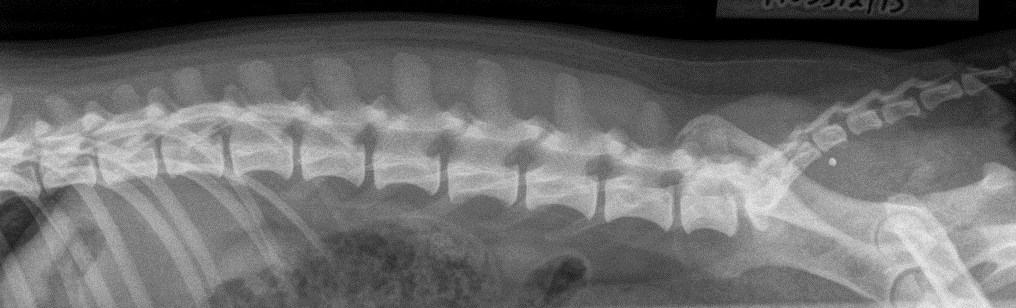

Jackrussellinterrierien selkä- ja lonkkakuvaus KEK Russelikamppis

Jackrussellinterrierien virallinen selkä- ja lonkkaröntgenkuvaus

Lonkat

Kaularanka

Rintaranka